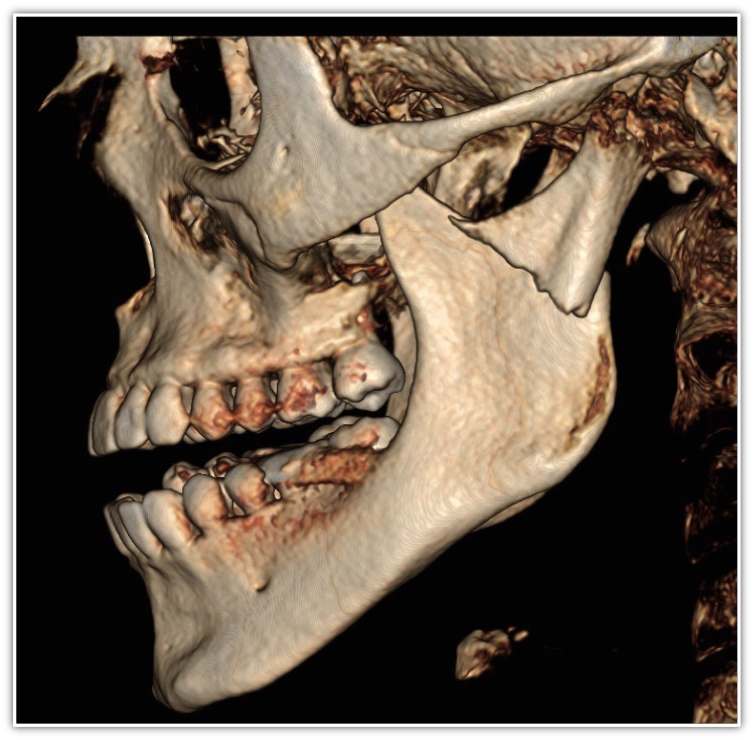

Doctors who have CBCT can use it for anatomic assessment of the airway and adjacent structures, and can thereby identify patients at risk for obstruction. Because these scans also include the jaws, teeth, cranial base, spine, and facial soft tissues, there is an opportunity to evaluate the functional and developmental relationships between these structures13 (Figure 5).

Figure 5. CBCT technology looks beyond the oral cavity to offer the clinician a broader picture that can be useful in diagnosing airway obstructions and disorders of the craniofacial and oropharyngeal anatomy.

Figure 5